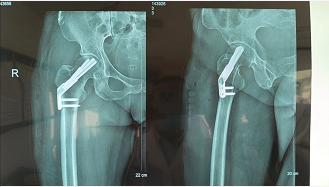

股骨颈骨折(左图)和股骨粗隆间骨折(右图)